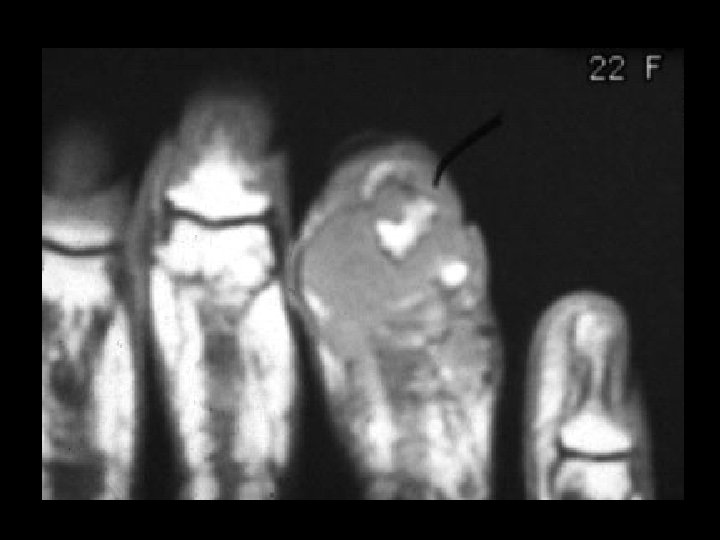

Giant cell tumor • Findings: – soft tissue mass destroying the tuft • ddx: – osteomyelitis – metastasis – chondrosarcoma